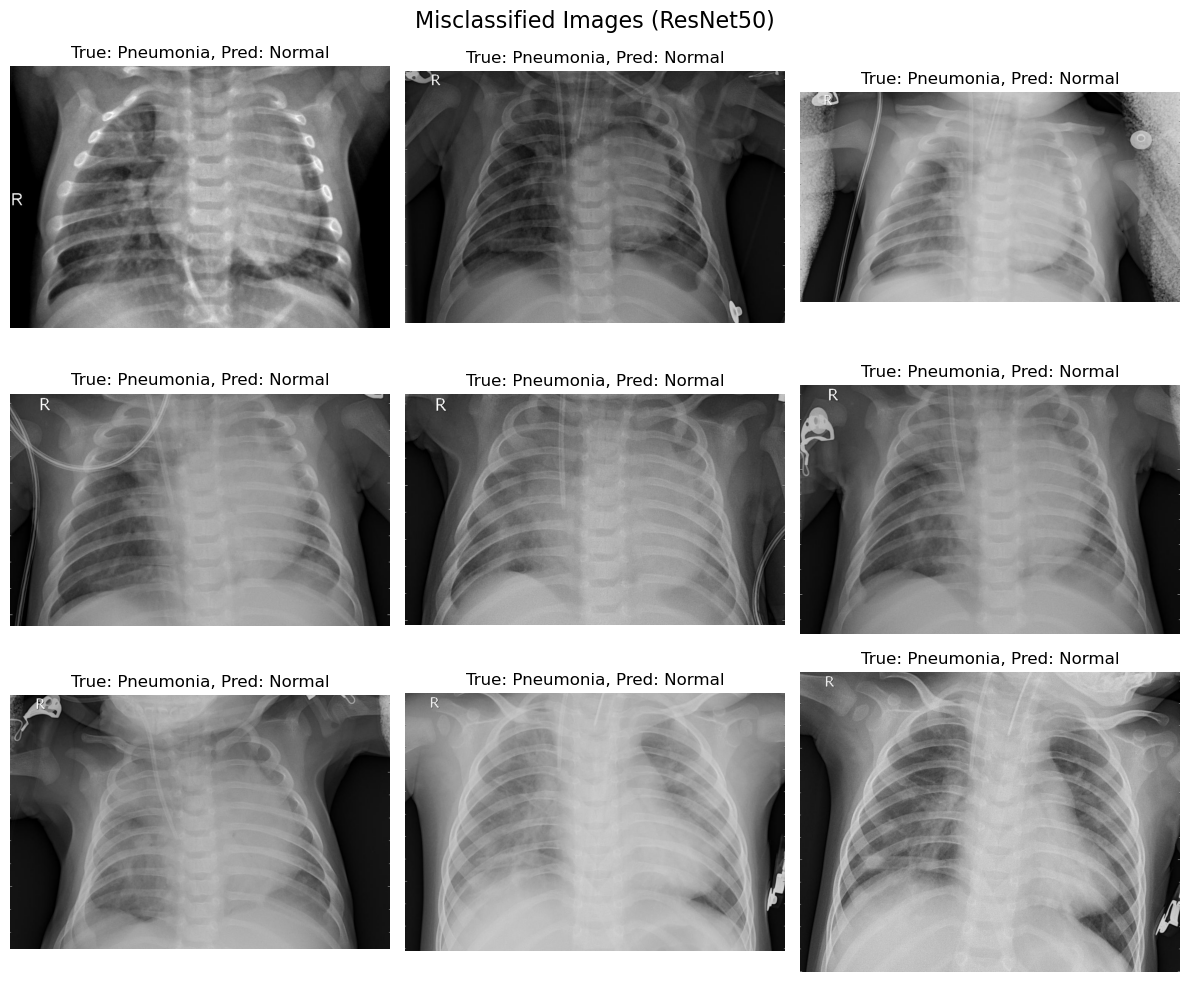

The comparison of the misclassified images from the two models, EfficientNetB0 and ResNet50, provides valuable insights into the strengths and weaknesses of both approaches in diagnosing pneumonia from chest X-ray images.

The confusion matrices and per-class accuracy reveal the following:

ResNet50:

i. Normal Class: Achieved better accuracy for normal cases compared to EfficientNetB0, with fewer false negatives.

ii. Pneumonia Class: Maintained a balanced trade-off between precision and recall, suggesting more reliable generalization.

Model Selection:

i. While both models perform well, ResNet50 is the recommended choice for practical applications due to its ability to minimize misclassifications and provide consistent performance.

i. Misclassifications must be studied in greater detail, as false negatives (pneumonia classified as normal) have significant consequences in clinical decision-making.

ii. A system incorporating ResNet50 with additional interpretability techniques (e.g., Grad-CAM or LIME) could support radiologists in identifying critical cases.

The comparative analysis highlights ResNet50 as the superior model for diagnosing pneumonia, with its deeper architecture enabling better feature extraction and classification performance. However, EfficientNetB0 remains a valuable alternative in scenarios where computational efficiency is a priority. Future work should explore advanced fine-tuning and ensemble methods to further enhance diagnostic accuracy.